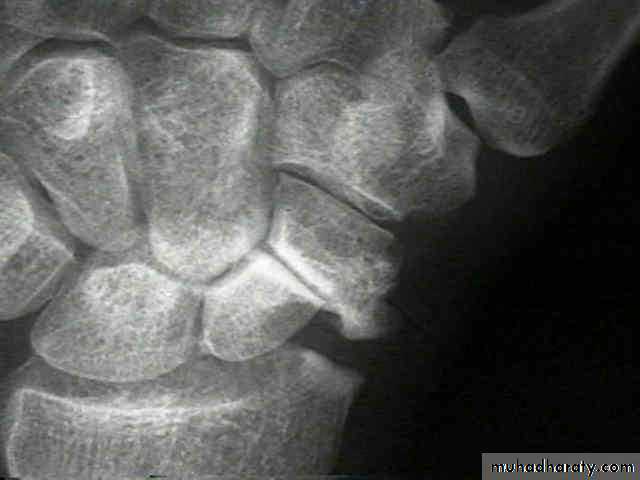

X-ray

Anteroposterior, lateral and oblique views are all essential; often a recent fracture shows only in the oblique view. Usually the fracture line is transverse,and through the narrowest part of the bone (waist), but it may be more proximally situated (proximal pole fracture). Sometimes only the tubercle of the scaphoid is fractured.Treatment

Scaphoid frcature